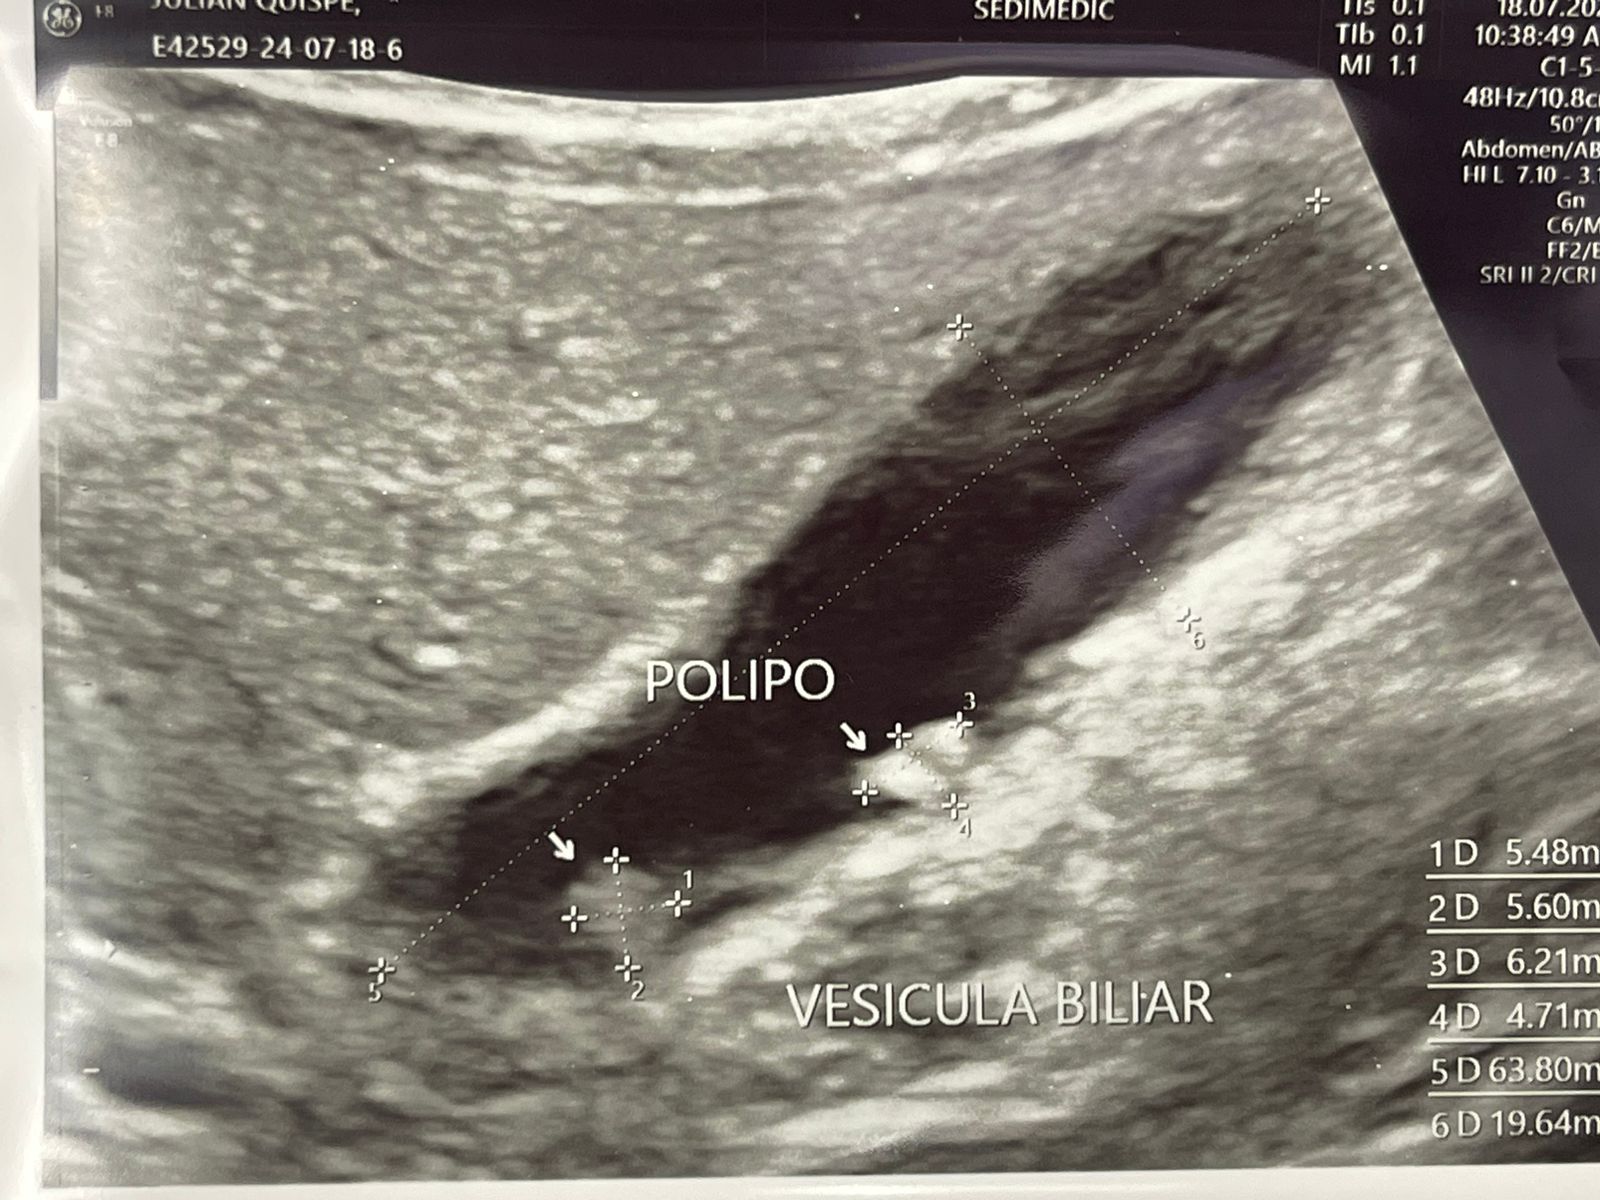

Patologías Quirúrgicas